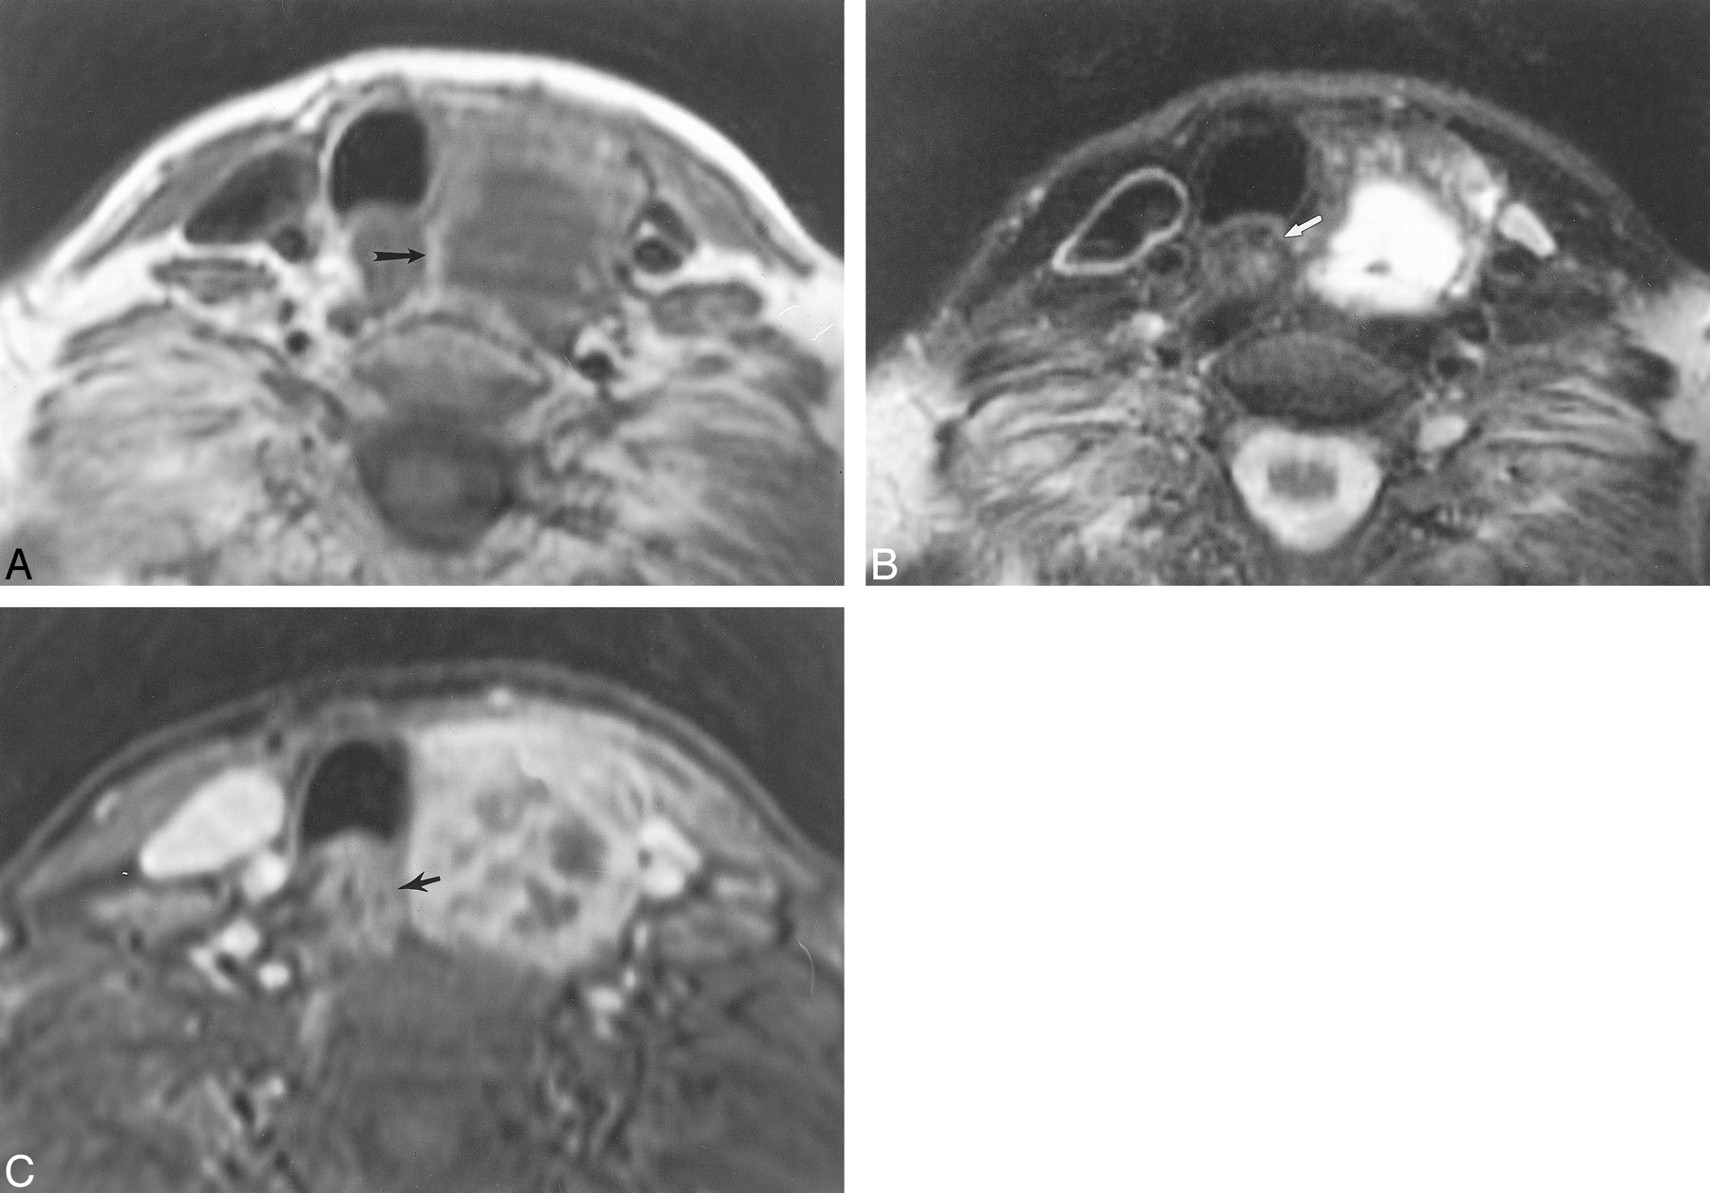

This 62-year-old man with metastatic laryngeal carcinoma to cervical lymph nodes had surgically proven esophageal invasion.

A, Axial T1-weighted image (700/17) shows obliteration of the fat plane between the mass (arrowheads) and the right lateral esophageal wall. There is focal wall thickening of the esophagus (white arrow). The esophageal lumen is distended with air (black arrow). The mass abuts the esophageal wall for less than 180o.

B, Axial T2-weighted image (4000/80) demonstrates increased esophageal wall signal (arrow) adjacent to the mass.

C, Axial enhanced 3D FMPSPGR image (235/21; flip angle, 90o) shows increased enhancement of the esophageal wall (arrow) as well as diffuse enhancement of the adjacent mass.